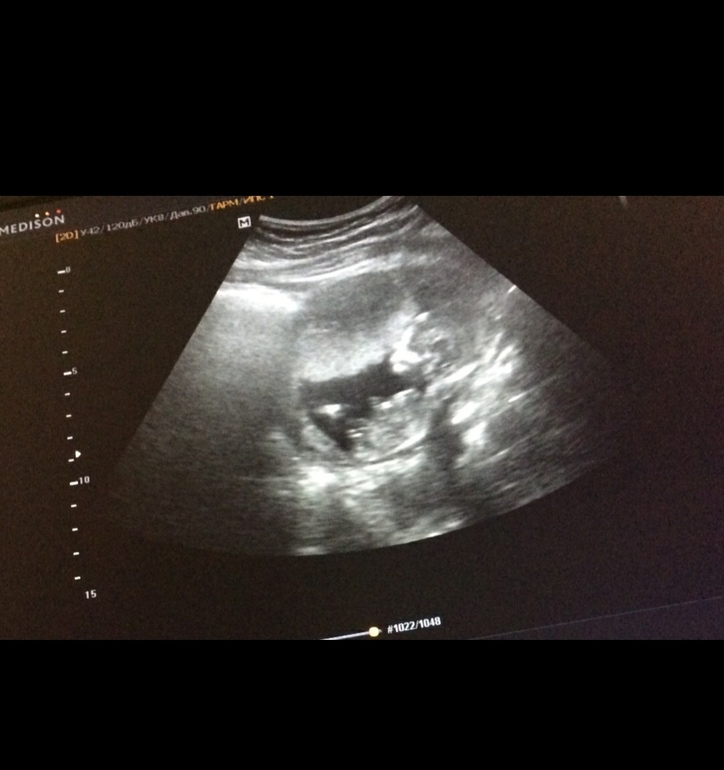

Да мне уже на УЗИ сказали, что точно мальчик, просто стало любопытно🤔

Мне почему-то сразу показался мальчуган 🙈

Хотелось другой пол) Пол на 16 недели